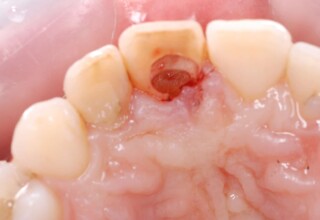

Dark root canal teeth

A rare case of dark root canal teeth with additional external absorption on the central incisor. After removal of the affected tissues of the central incisor, the tooth could not be directly bleached because of the soft tissue contact. The tooth was initially restored to provide the original tooth form, then it was bleached and the restoration was finalized.

Initial appearance